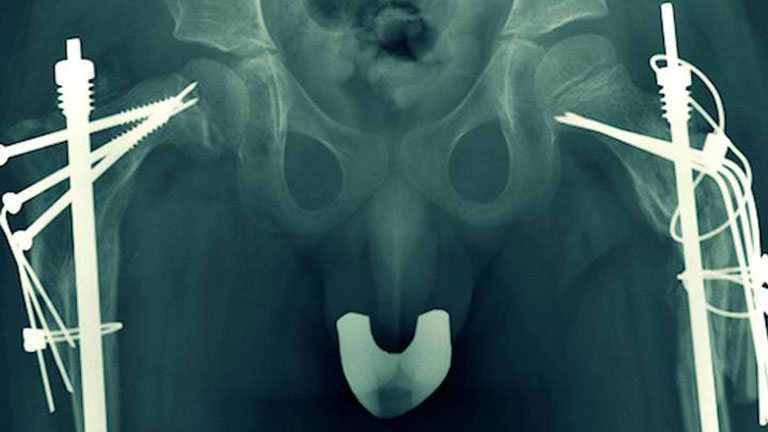

Cada 6 de mayo se celebra en todo el mundo el día de la osteogénesis imperfecta, que afecta a medio millón de personas. Y éste es el objetivo primordial que persigue “Frágil, un camino de cristal”, un magnífico trabajo que emite Documentos TV sobre los huesos de cristal y la realidad vivida a diario por los afectados y sus familias. 'Frágil, camino de cristal' se emite en Documentos TV el domingo 4 de mayo de 2014 a las 23:00 h. en La 2 de TVE